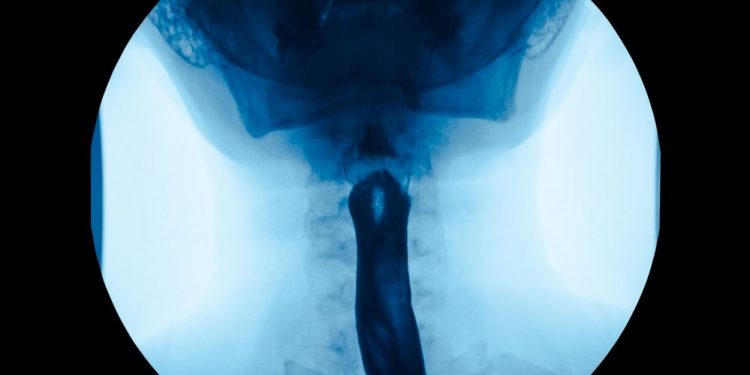

You may also be given a test called an endoscopy, which is a thin tube with a camera attached that lets the doctor examine your digestive tract. They may also remove a small amount of tissue (biopsy) to check for signs of cancer.